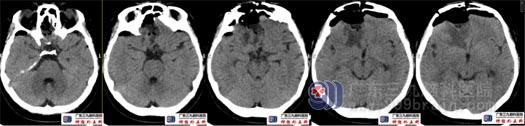

术后复查头颅CT术腔未见血肿,肿瘤全切除。

术后头颅MRI示肿瘤全切。